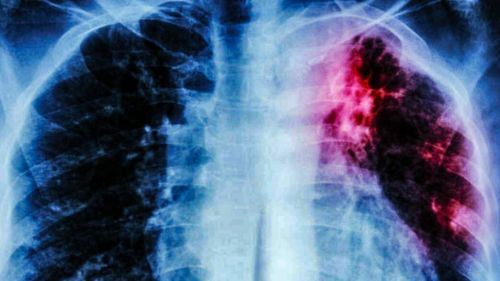

Kementerian Kesihatan Malaysia (KKM) mengesahkan kewujudan satu kluster Tuberkulosis (tibi) di Kota Tinggi pada 25 Januari lalu, selepas 33 kes positif dikesan hasil saringan terhadap 804 kontak rapat setakat 4 Februari. Pengesahan itu diumumkan sendiri oleh Menteri Kesihatan, Datuk Seri Dr Dzulkefly Ahmad, yang memaklumkan bahawa pasukan KKM kini berada di lapangan bagi melaksanakan langkah pencegahan secara agresif.

Tuberkulosis, atau lebih dikenali sebagai batuk kering, adalah penyakit berjangkit yang disebabkan oleh bakteria Mycobacterium tuberculosis. Ia merebak melalui udara apabila pesakit batuk atau bersin, terutama kepada individu yang mempunyai kontak rapat dalam tempoh lama.